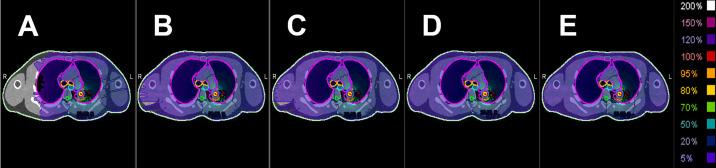

Volumetric modulated arc therapy (VMAT) for lung cancer involves complex multileaf collimator (MLC) motion, which increases sensitivity to interplay effects with tumour motion. Current dynamic conformal arc methods address this issue but may limit the achievable dose distribution optimisation compared with standard VMAT. This study examined the clinical utility of a VMAT technique with monitor unit limits (VMATliMU) to mimic conformal arc delivery and reduce interplay effects while maintaining plan quality. VMATliMU was implemented by applying monitor unit limitations during VMAT reoptimisation to minimise MLC encroachment into target volumes. Using mesh-type reference computational phantom CT images, treatment plans were generated for a simulated stage I lung cancer case prescribed to 45 Gy in three fractions. VMATliMU, conventional VMAT, VMAT with leaf speed limitations, dynamic conformal arc therapy, and constant dynamic conformal arc therapy were compared. Plans were optimised for multiple isodose line prescriptions (50%, 60%, 70%, 80%, and 90%) to investigate the impact of dose distribution. Evaluation parameters included MLC positional accuracy using area difference ratios, dosimetric indices, gradient metrics, and organ-at-risk doses. VMATliMU prevented MLC encroachment into the internal target volume across 60%-90% isodose lines, showing superior MLC accuracy compared with other methods. At the challenging 50% isodose line, VMATliMU had 4.5 times less intrusion than VMAT with leaf speed limits. VMAT plans had better dosimetric indices than dynamic conformal arc plans. VMATliMU reduced monitor units by 5.1%-19.2% across prescriptions. All plans met the clinical dose constraints, with the aortic arch below tolerance and acceptable lung doses. VMATliMU combines VMAT's dosimetric benefits with the dynamic conformal arcs's simplicity, minimising MLC encroachment while maintaining plan quality. Reduced monitor units lower low-dose exposure, treatment time, and interplay effects. VMATliMU is usable in existing planners with monitor unit limits, offering a practical solution for lung stereotactic body radiation therapy.

肺癌的容积调强弧形放疗(VMAT)涉及复杂的多叶准直器(MLC)运动,这增加了对与肿瘤运动相互作用效应的敏感性。当前的动态适形弧形放疗方法解决了这个问题,但与标准VMAT相比,可能会限制可实现的剂量分布优化。本研究探讨了一种带有监测单位限制的VMAT技术(VMATliMU)的临床实用性,该技术可模拟适形弧形放疗并减少相互作用效应,同时保持计划质量。VMATliMU是通过在VMAT重新优化过程中应用监测单位限制来实现的,以尽量减少MLC侵入靶区体积。使用网格型参考计算体模CT图像,为一例模拟的I期肺癌病例制定治疗计划,处方剂量为45 Gy,分三次照射。比较了VMATliMU、传统VMAT、有叶片速度限制的VMAT、动态适形弧形放疗和恒定动态适形弧形放疗。针对多个等剂量线处方(50%、60%、70%、80%和90%)对计划进行优化,以研究剂量分布的影响。评估参数包括使用面积差异比的MLC位置准确性、剂量学指标、梯度度量和危及器官剂量。VMATliMU在60% - 90%等剂量线上防止了MLC侵入内部靶区体积,与其他方法相比,显示出更高的MLC准确性。在具有挑战性的50%等剂量线上,VMATliMU的侵入比有叶片速度限制的VMAT少4.5倍。VMAT计划的剂量学指标优于动态适形弧形放疗计划。VMATliMU在所有处方中减少了5.1% - 19.2%的监测单位。所有计划均符合临床剂量限制,主动脉弓低于耐受剂量,肺部剂量可接受。VMATliMU将VMAT的剂量学优势与动态适形弧形放疗的简单性相结合,在保持计划质量的同时最大限度地减少了MLC侵入。减少的监测单位降低了低剂量照射、治疗时间和相互作用效应。VMATliMU可在具有监测单位限制的现有计划系统中使用,为肺部立体定向体部放疗提供了一种实用的解决方案。